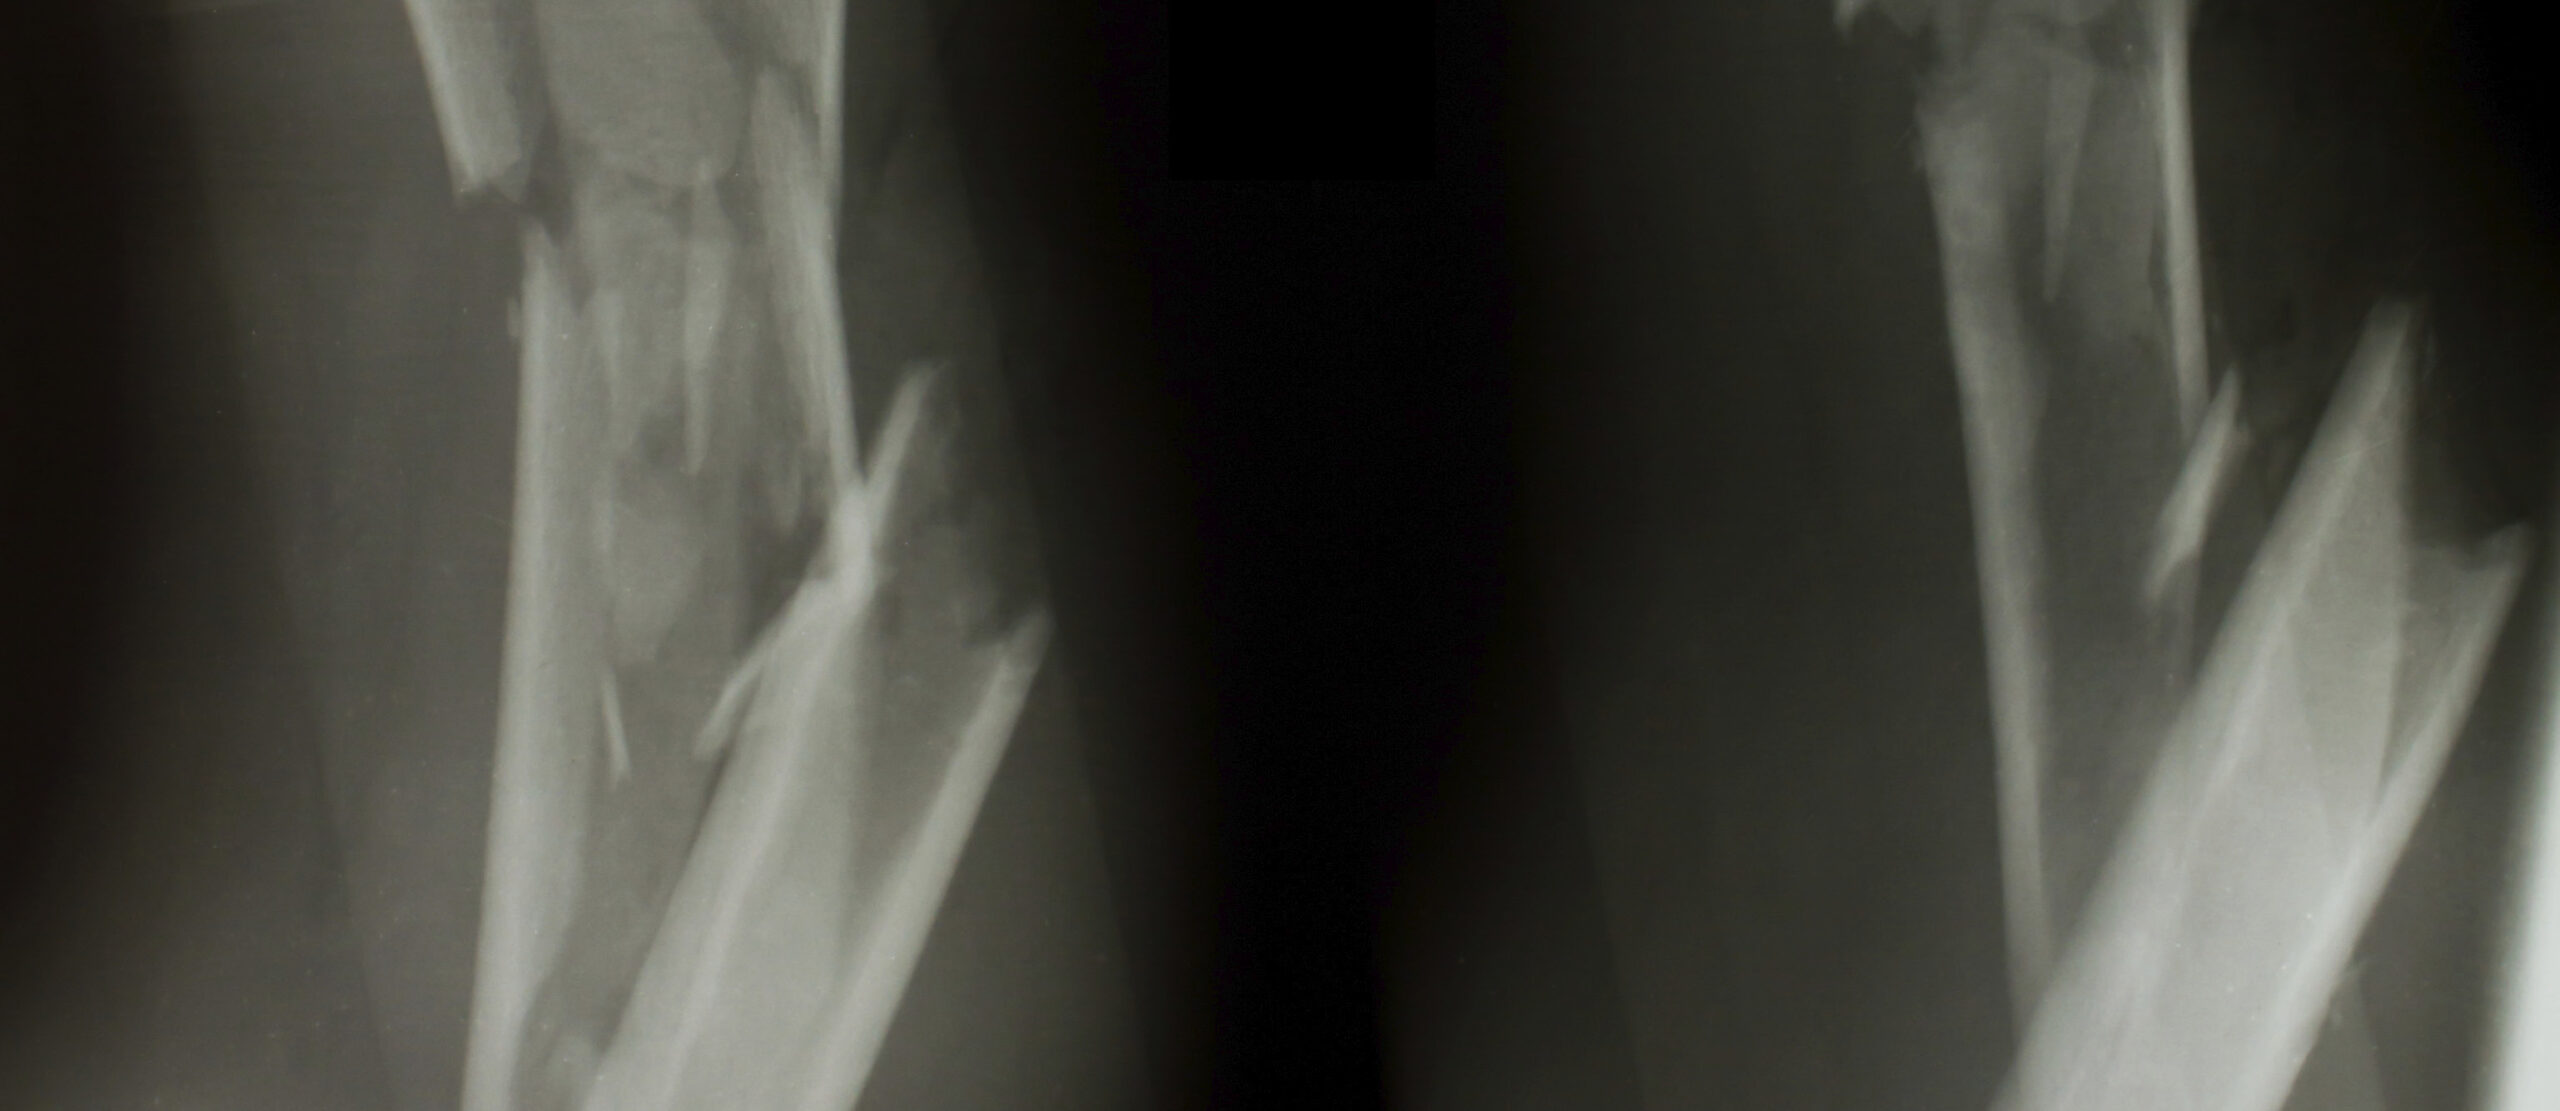

Diaphyseal (long bone) fractures are a common sequellae of traumatic events. These fractures, occurring in the femur, tibia, fibula, humerus, radius, ulna, and long bones of the hands and feet, may be secondary to either direct or indirect forces. Direct trauma often results in open fractures. Indirect rotational forces may result in spiral or spiral wedge diaphyseal fractures with a large surface of bone contact that aids healing. Additionally, these forces often result in less soft tissue and periosteal damage, promoting good healing. Bending forces result in oblique wedge fractures. The degree of trauma in these fractures is usually more significant resulting in a larger amount of damage to soft tissues and periosteum that inhibits healing. Direct forces upon the diaphysis result in a spectrum of fracture patterns including transverse fractures, fragmented wedge fractures, and complex fractures. The forces causing these fractures are often quite large and result in extensive soft tissue damage. These fractures are the most difficult to heal. The determination of fracture type predicts the degree of underlying potential soft tissue damage and provides a guideline for determining the timing of surgery as well as reduction and fixation technique with the ultimate goal of restoration of bone length as well as axial and rotational alignment with respect to the flanking joints.

Radiography is the mainstay in fracture analysis at any stage. It provides an overall assessment of fracture morphology and provides insight into all potential features of a fracture as it evolves over time. Radiographic analysis requires at least two views for proper assessment, as fractures not seen on one view may be glaringly apparent on another view. Additionally, different views afford different perspectives on fracture analysis, thereby permitting the physician to better detect such complications as displaced fragments, subtle bone destruction, malunion, or hardware failure. However, as radiographic analysis invariably superimposes anatomy in the generation of an image, this modality suffers when more detailed and precise assessment is required.